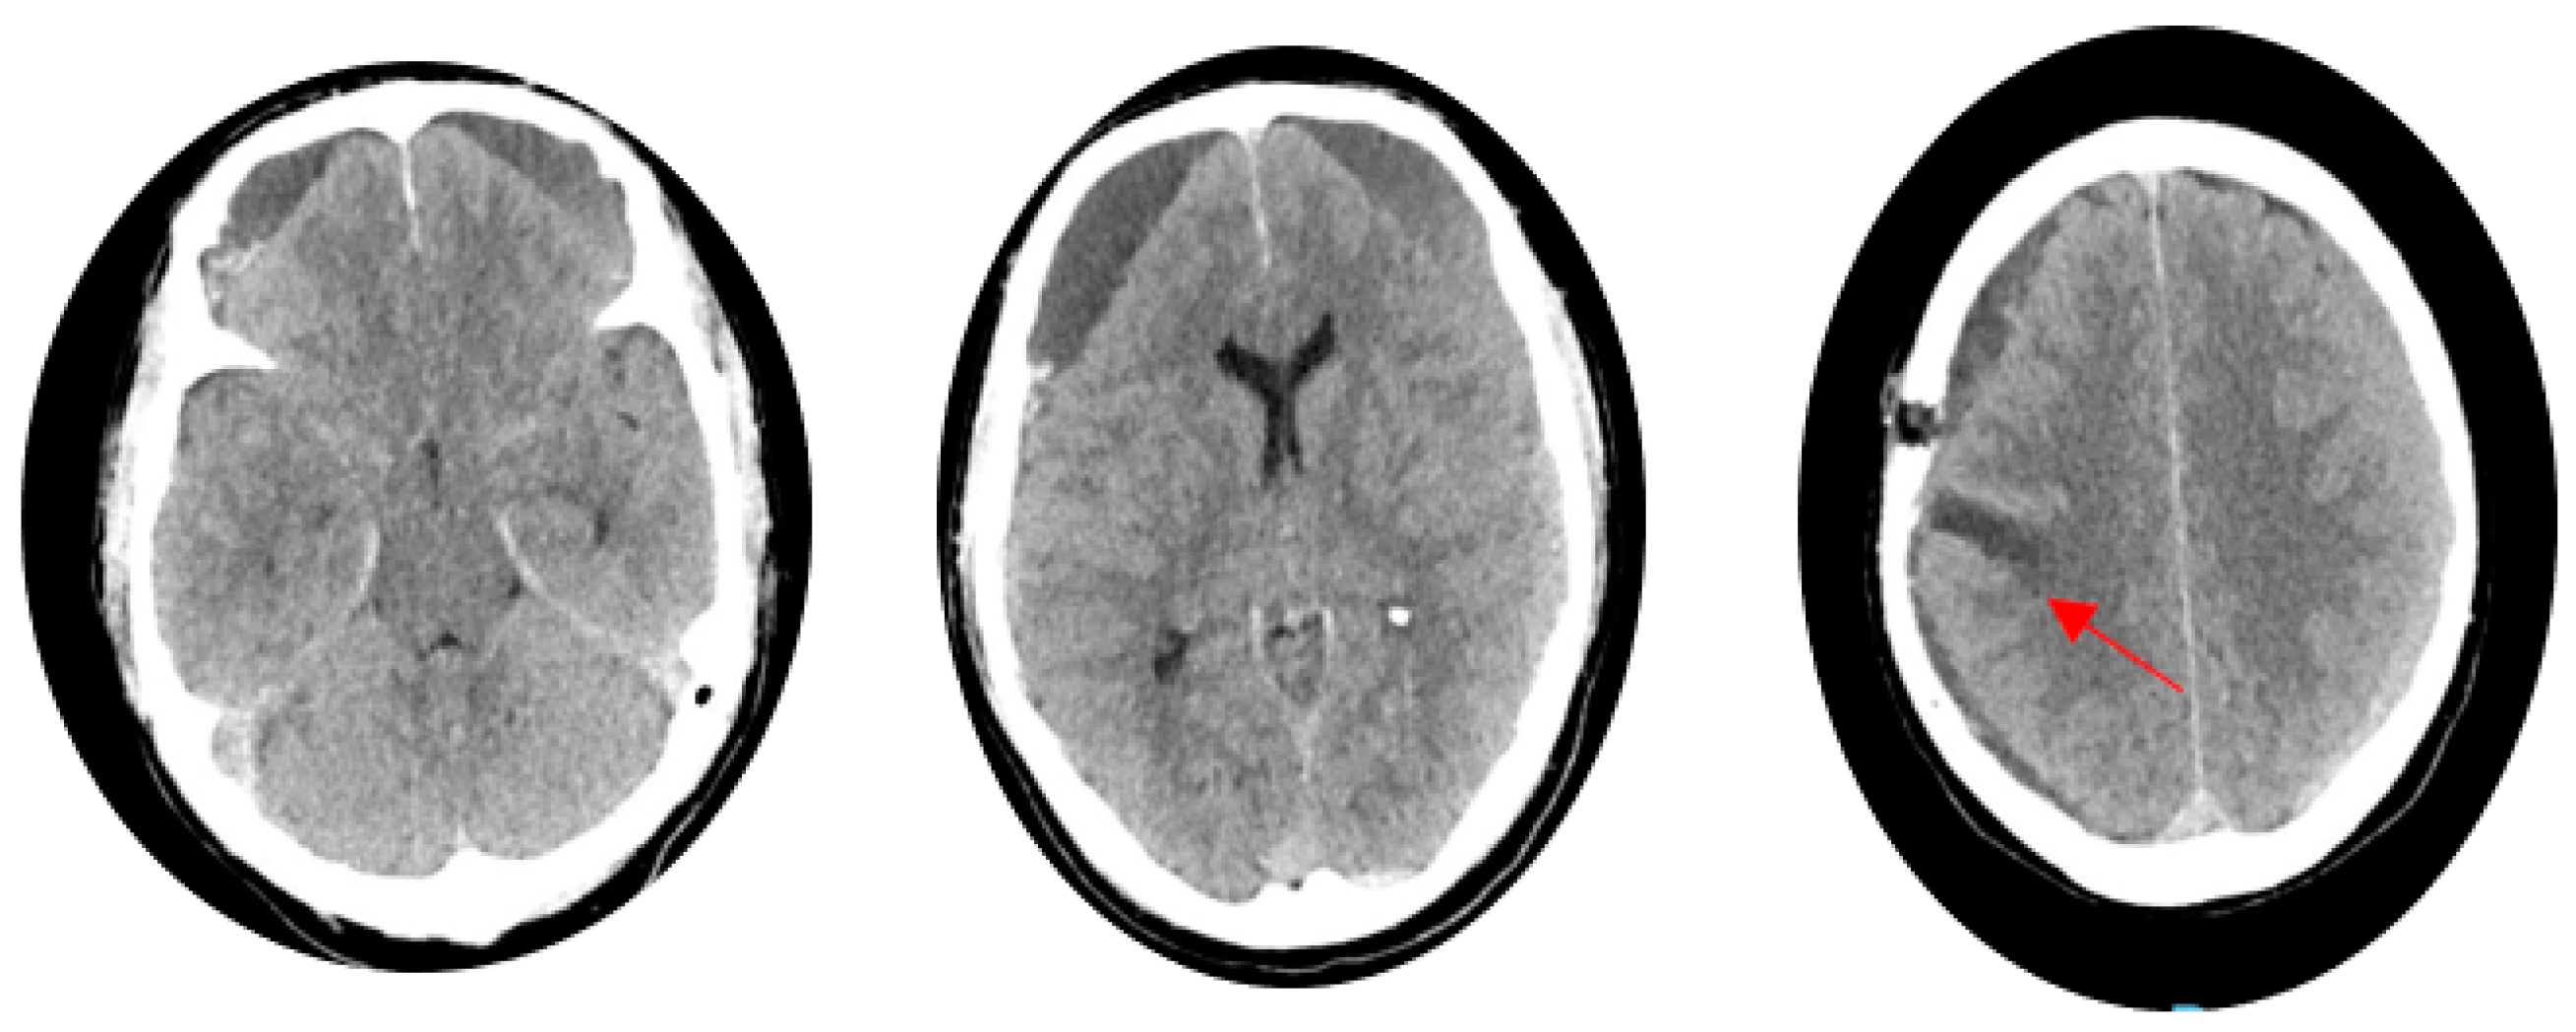

2. Case Report